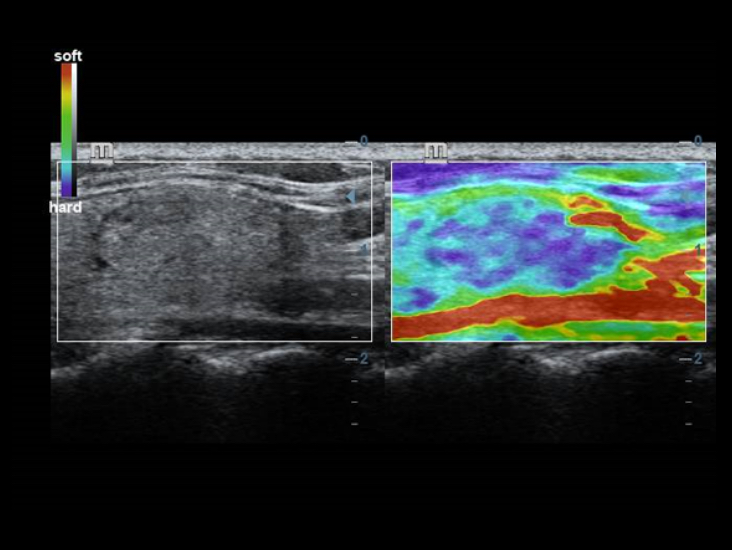

Teknologi pencitraan klasik: meningkatkan mutu diagnosis

Dengan penerapan teknologi pencitraan klasik, yang dimigrasikan dari sistem ultrasound yang sudah terbukti, DC-40 dengan Full HD memberikan peningkatan mutu akan detail gambar.

- iClear (teknologi pencitraan reduksi speckle)

- PSH (Pencitraan Phase Shift Harmonic)

- iBeam: Teknologi spatial-compounding imaging